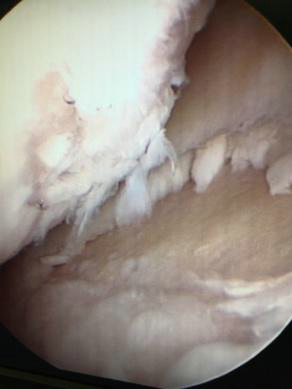

第三阶梯的治疗方案是微创的关节镜手术,对于关节内滑膜增生较为严重、合并有半月板撕裂或游离体的病人效果显著。关节镜手术创伤小,术后恢复快,受到很多患者的青睐。

膝关节镜微创手术修整损伤半月板、软骨组织